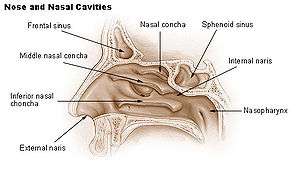

The frontal sinuses are situated behind the brow ridges. Sinuses are mucosa-lined airspaces within the bones of the face and skull. Each opens into the anterior part of the corresponding middle nasal meatus of the nose through the frontonasal duct which traverses the anterior part of the labyrinth of the ethmoid. These structures then open into the hiatus semilunaris in the middle meatus.

Paranasal sinuses Nose diagram

Nose diagram- Frontal sinus